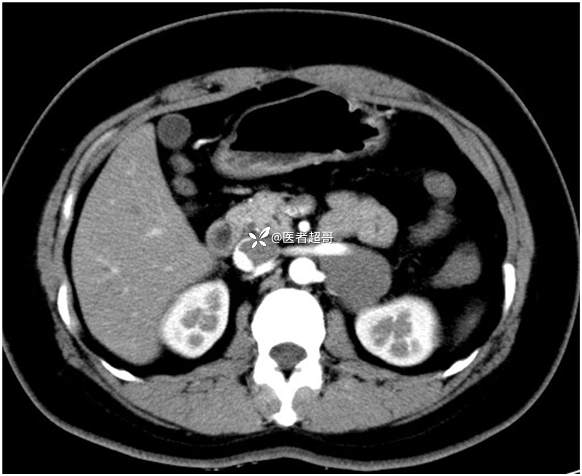

病例【影诊笔记711】女,23岁,体检发现左侧肾上腺占位,有病理,请赏析~~~

女,23岁,体检发现左侧肾上腺占位

肾上腺肿瘤 (112)